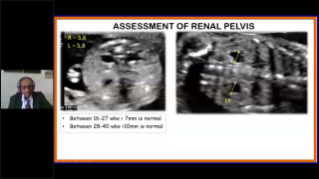

WomenŌĆÖs health is the foundation of health for all and is especially important for countries with aging populations and low fertility levels. MindrayŌĆÖs solution protects multiple life stages, including reproduction, prenatal and intrapartum, and postpartum pelvic floor, with accurate images and efficient and easy-to-use intelligent applications to help caring womenŌĆÖs health in all aspects and cycles.